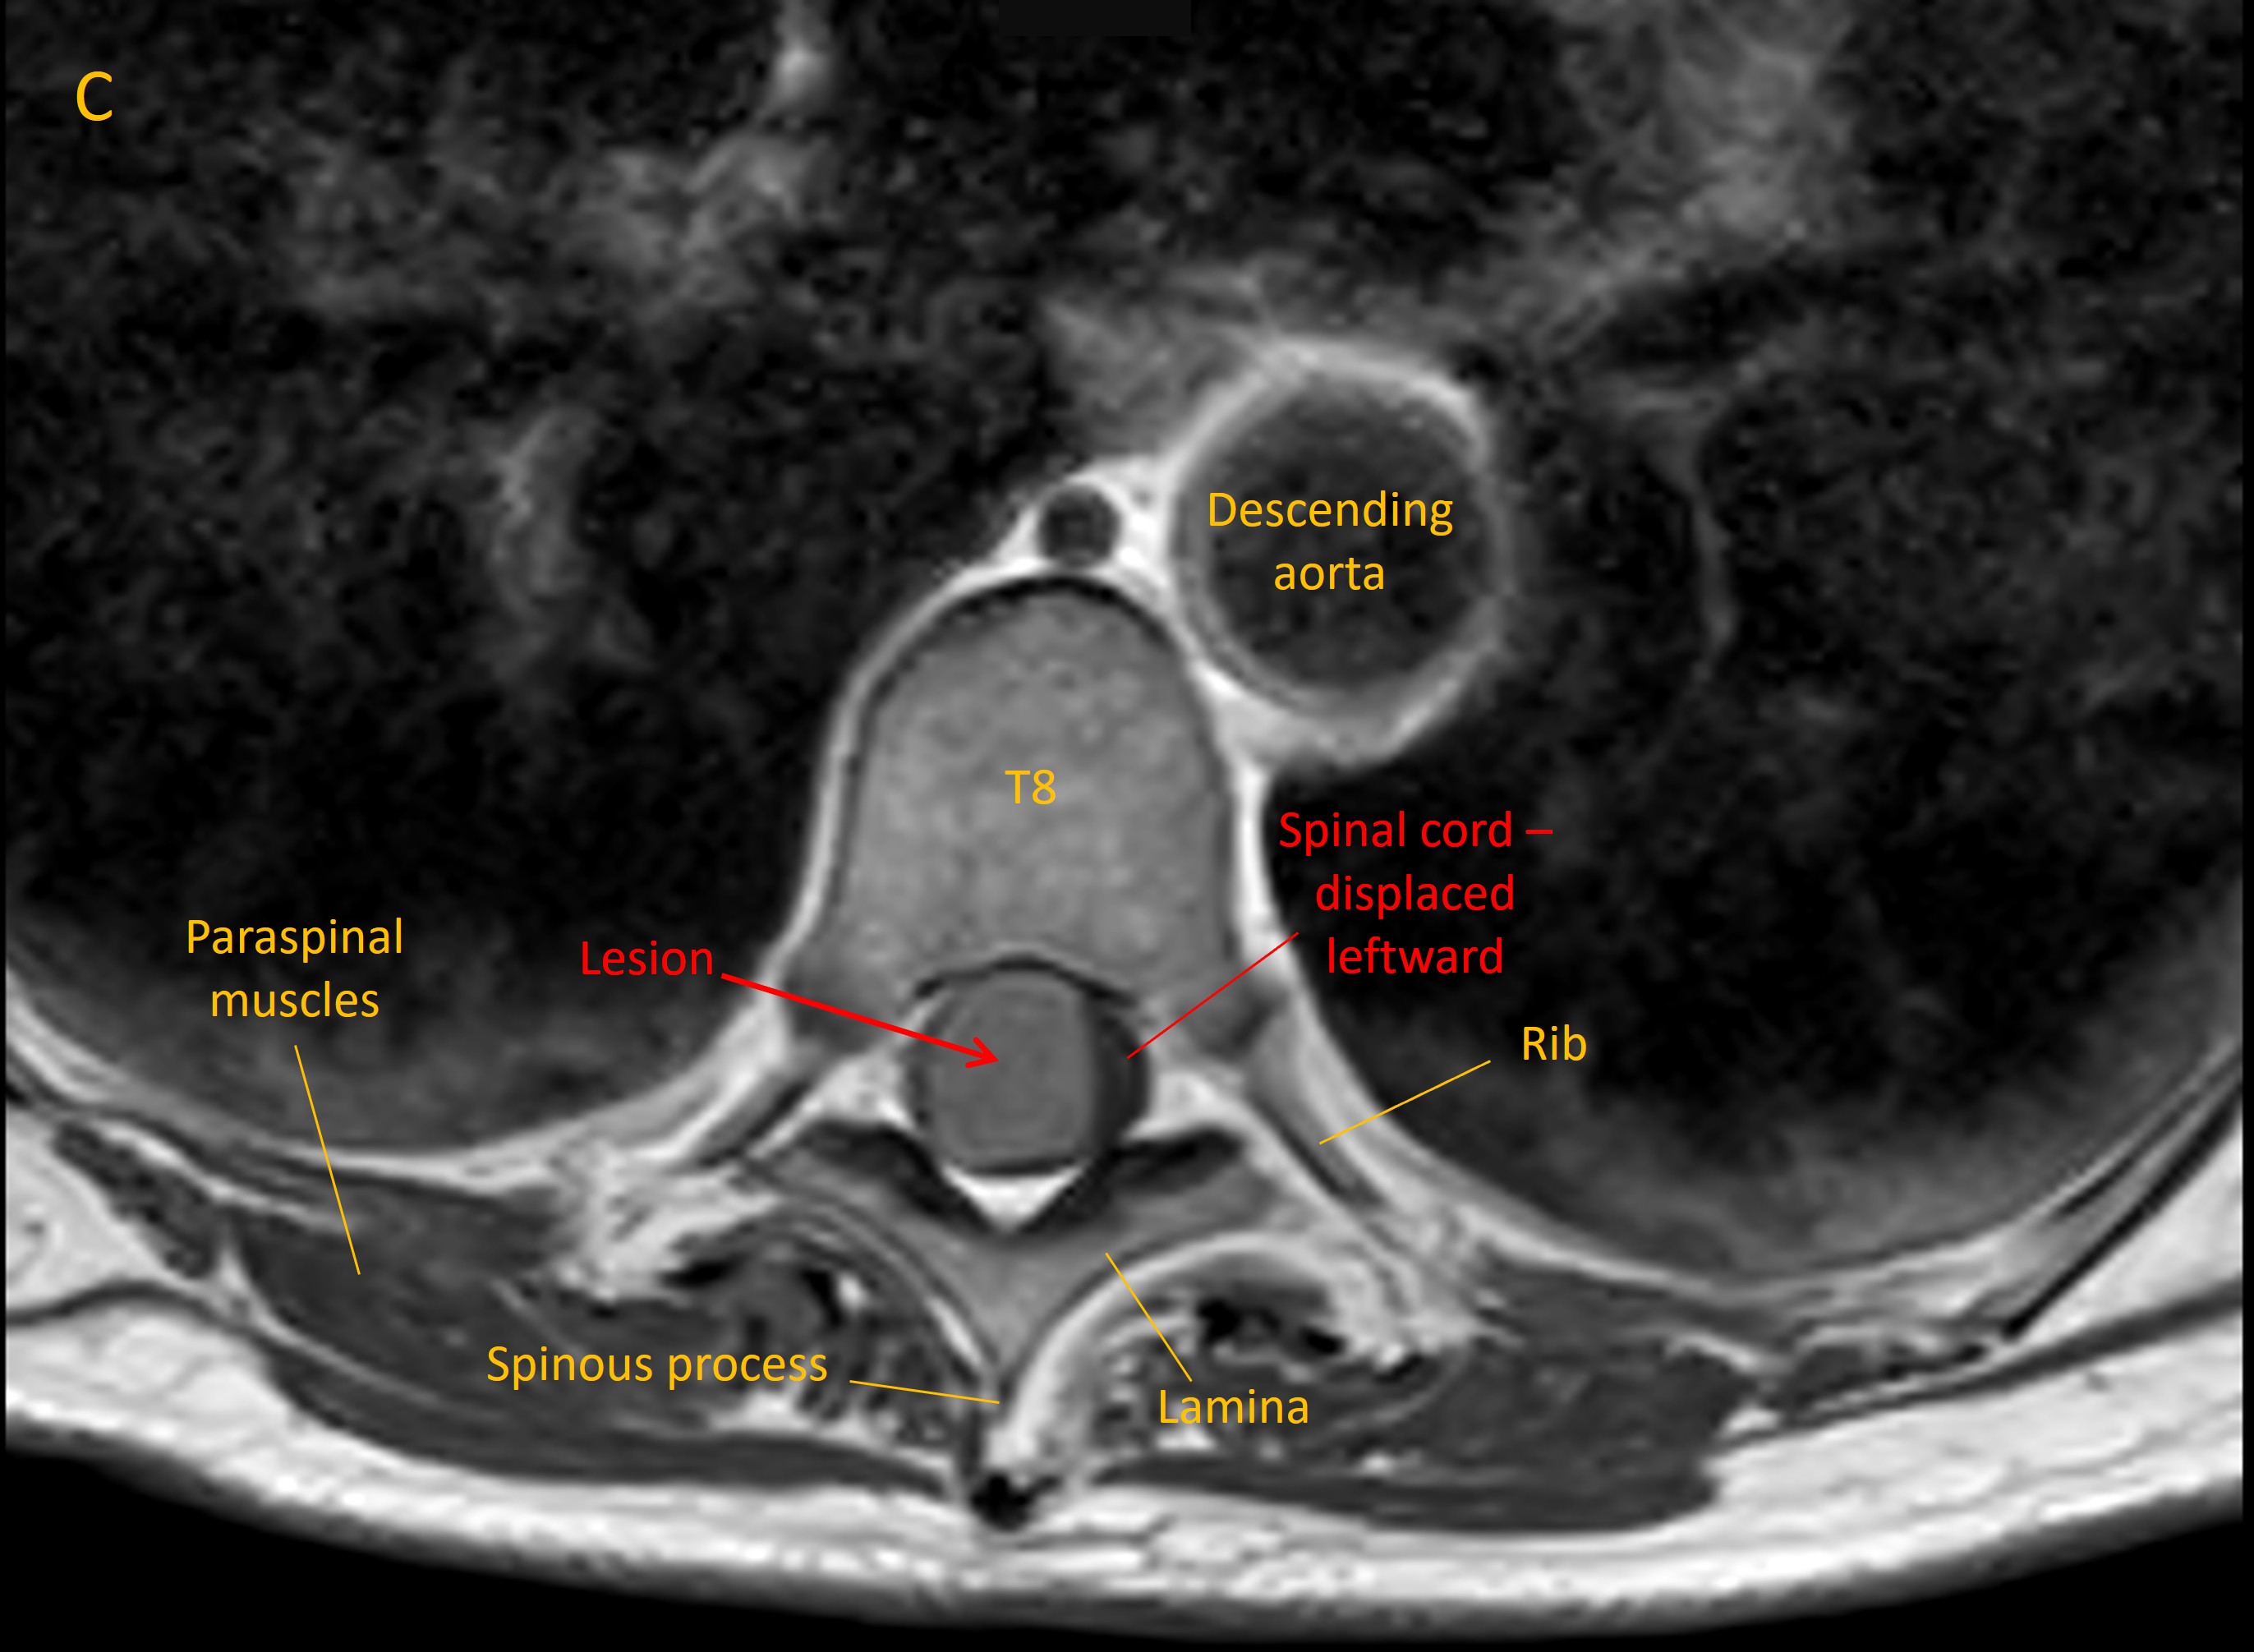

An MRI identified a lesion at T8/9 growing from the meningeal space (Image A, sagittal T2 MRI). This had homogenous contrast enhancement (B, T1 MRI with contrast). There was evidence of lateral displacement of the spinal cord (C, axial MRI).

Axial MRI

Imaging was consistent with a meningioma. Reassuringly there was no evidence of metastatic disease on body imaging.